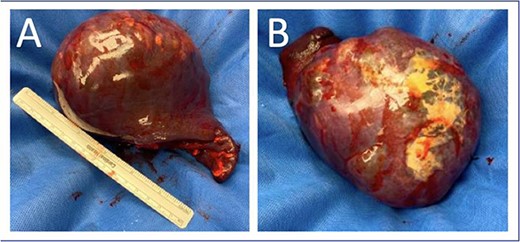

As part of his workup, he underwent an abdominal ultrasound showing a 12 cm cystic or hemorrhagic lesion, likely splenic in origin, with an adjacent 5.6 cm complex septated lesion within the spleen. Subsequent abdominal CT showed a 12 cm in greatest diameter complex cystic lesion within the spleen with peripheral and septal calcification with no solid enhancing component (Fig. 1). His blood work, including complete blood count, complete metabolic panel, and coagulation markers, were all within normal limits.

Preoperative (A) axial and (B) coronal abdominal CT images showing complex cystic splenic mass.